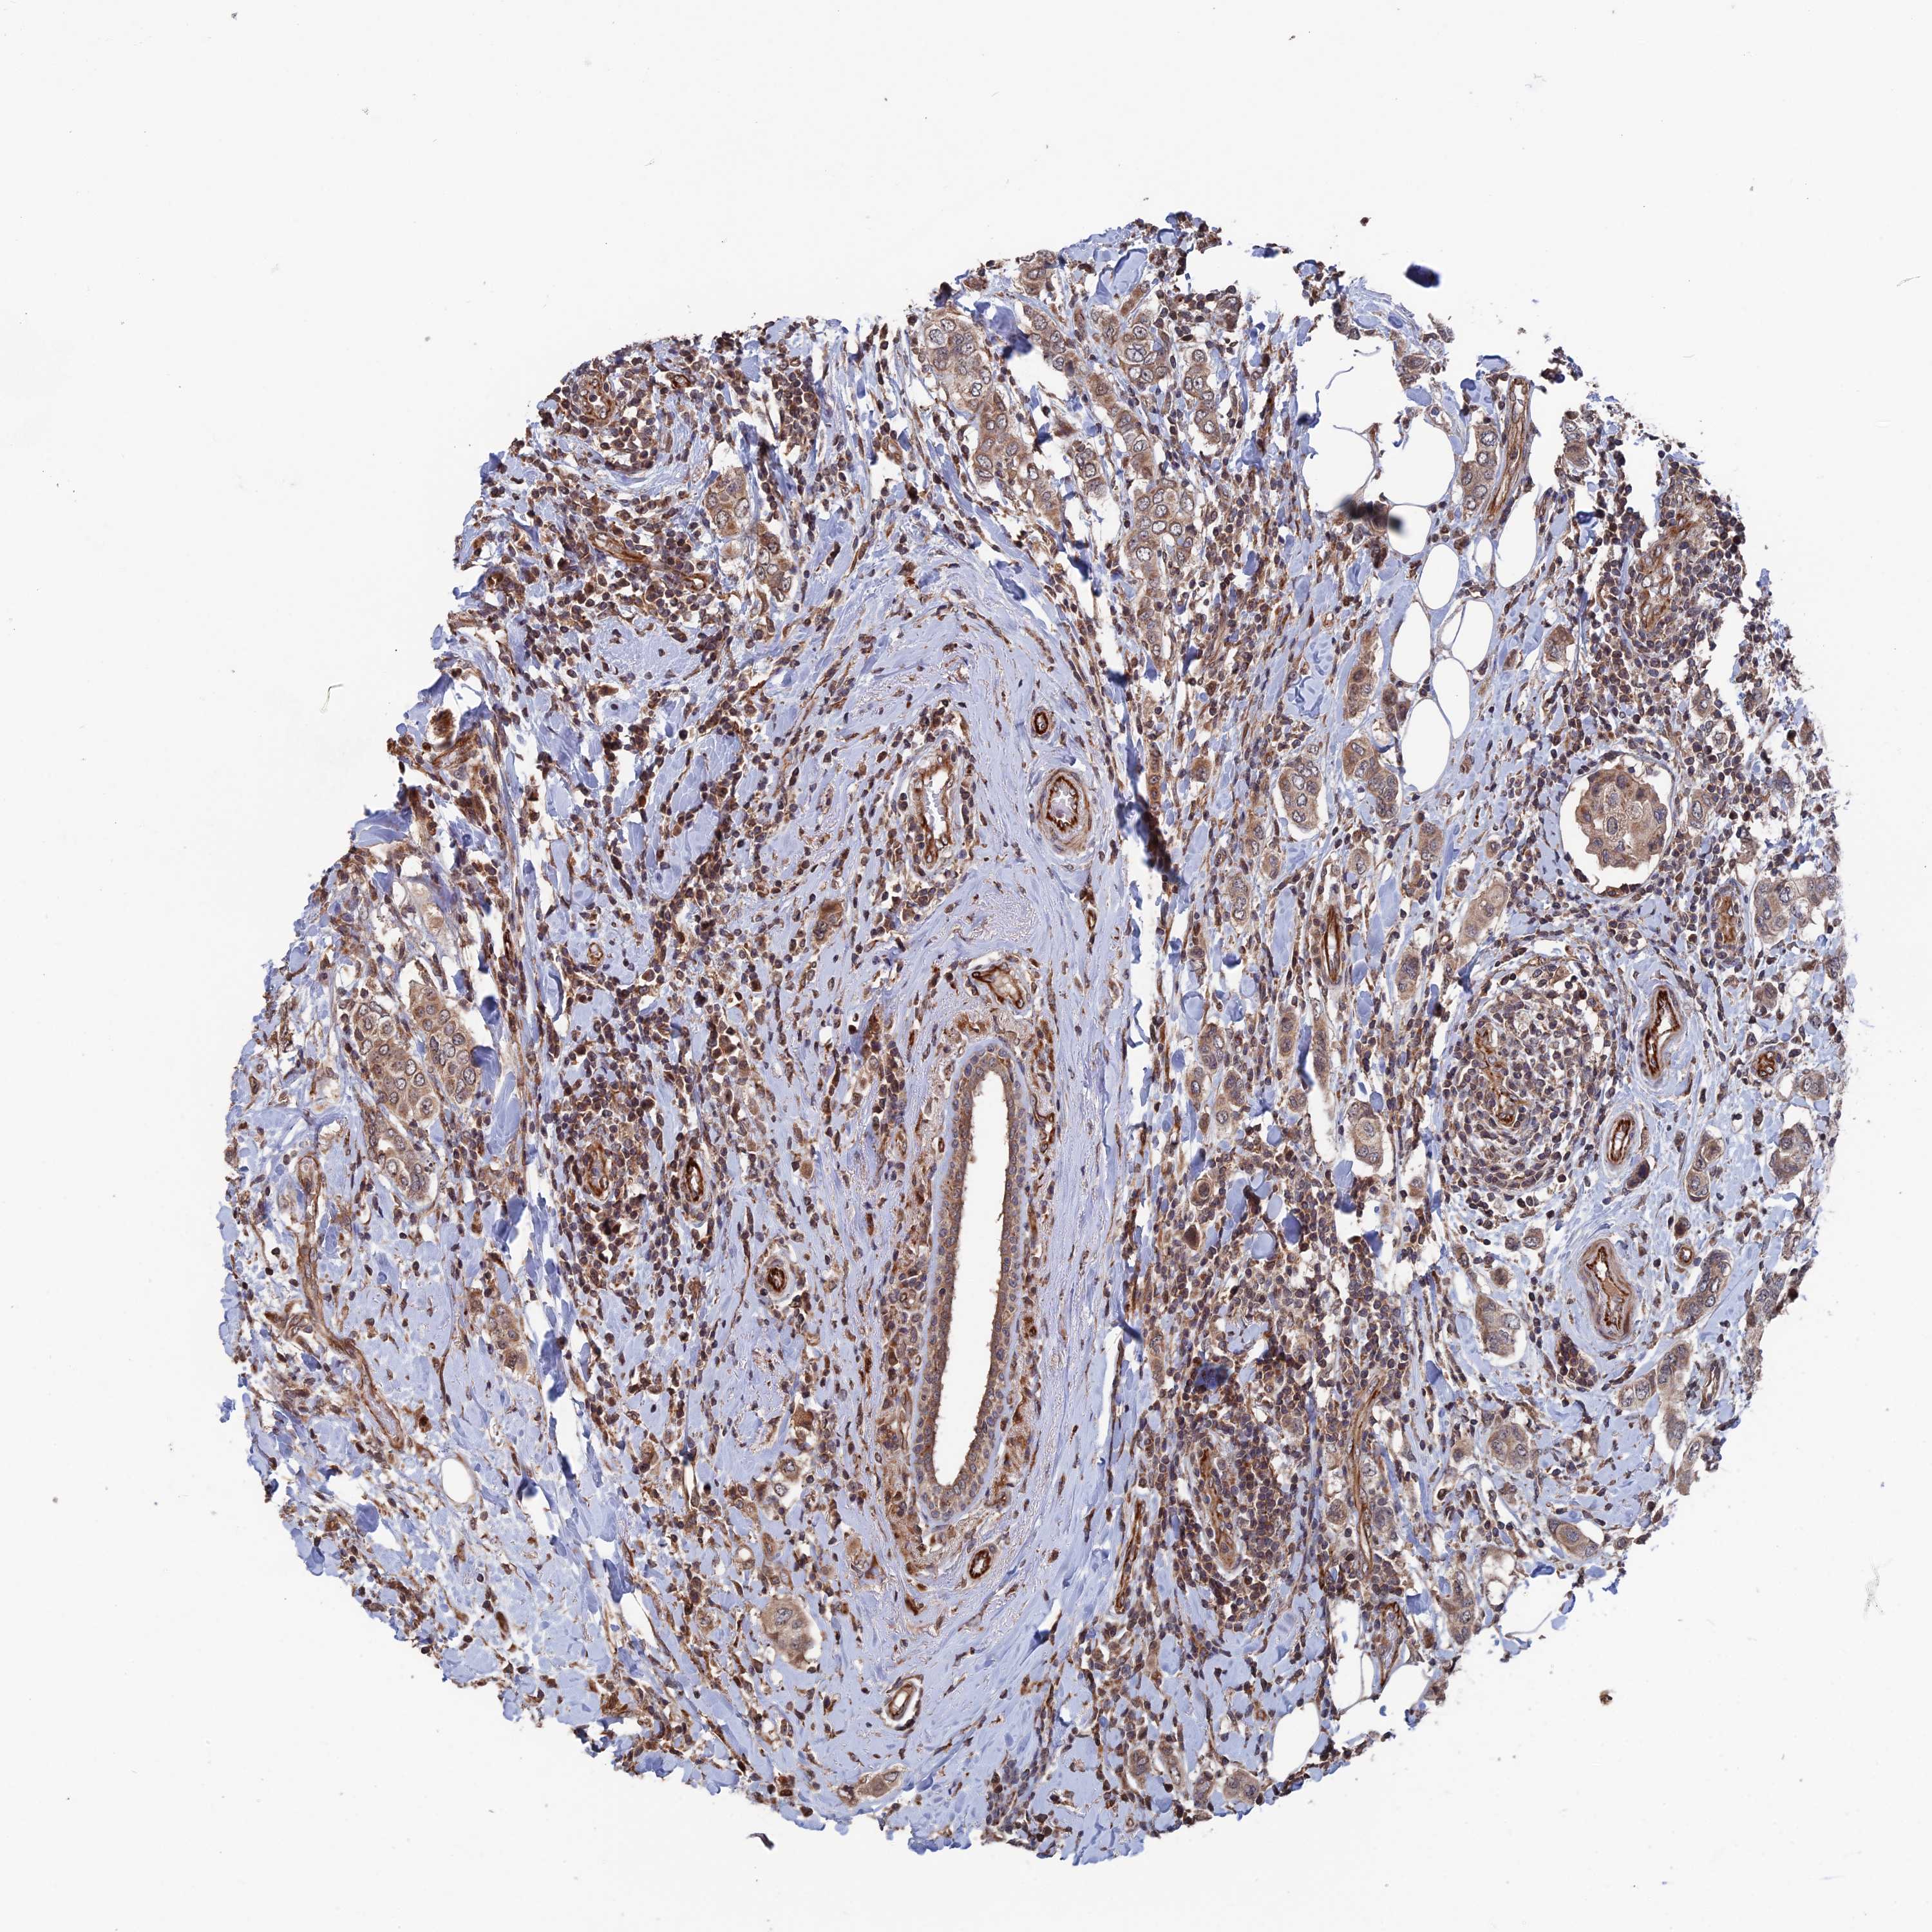

CANCER BREAST CANCER Show tissue menu

BRCA TCGA BRCA VALIDATION PROTEIN EXPRESSION